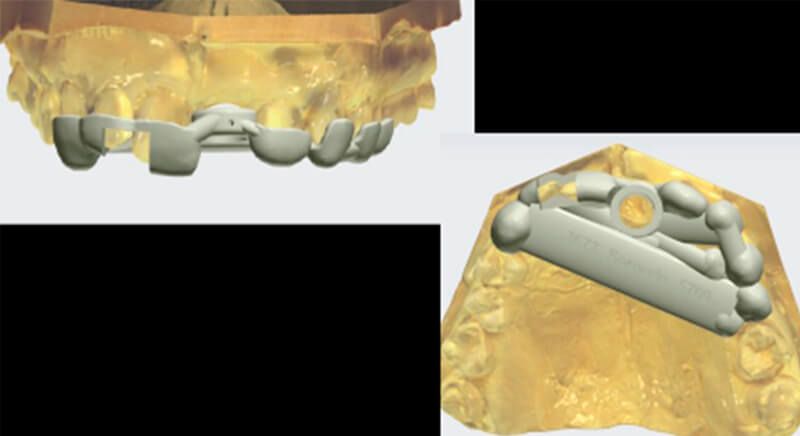

During the digital planning for the implant, with Implant Studio (3Shape) guided surgery software, significant bone defects due to the patient's anatomy were discovered. Placing the implant in the correct position for the prosthesis presented bone dehiscence in the vestibular area, and another bone defect in the palatine area due to the patient's large nasopalatine canal.

This information enabled us to rule out the option of surgery without a flap, as regeneration simultaneous to surgery would be needed, so the idea of using guided surgery was maintained.

The guided surgery was performed by lifting a full thickness mucoperiosteal flap. A Biomimetic Ocean CC implant, diameter 3.5mm and length 10mm, was inserted using the surgical guide in the ideal three-dimensional position and the defects were regenerated with xenograft and reabsorbable membrane, the nasopalatine duct on the palatine side and the area of dehiscence on the vestibular.